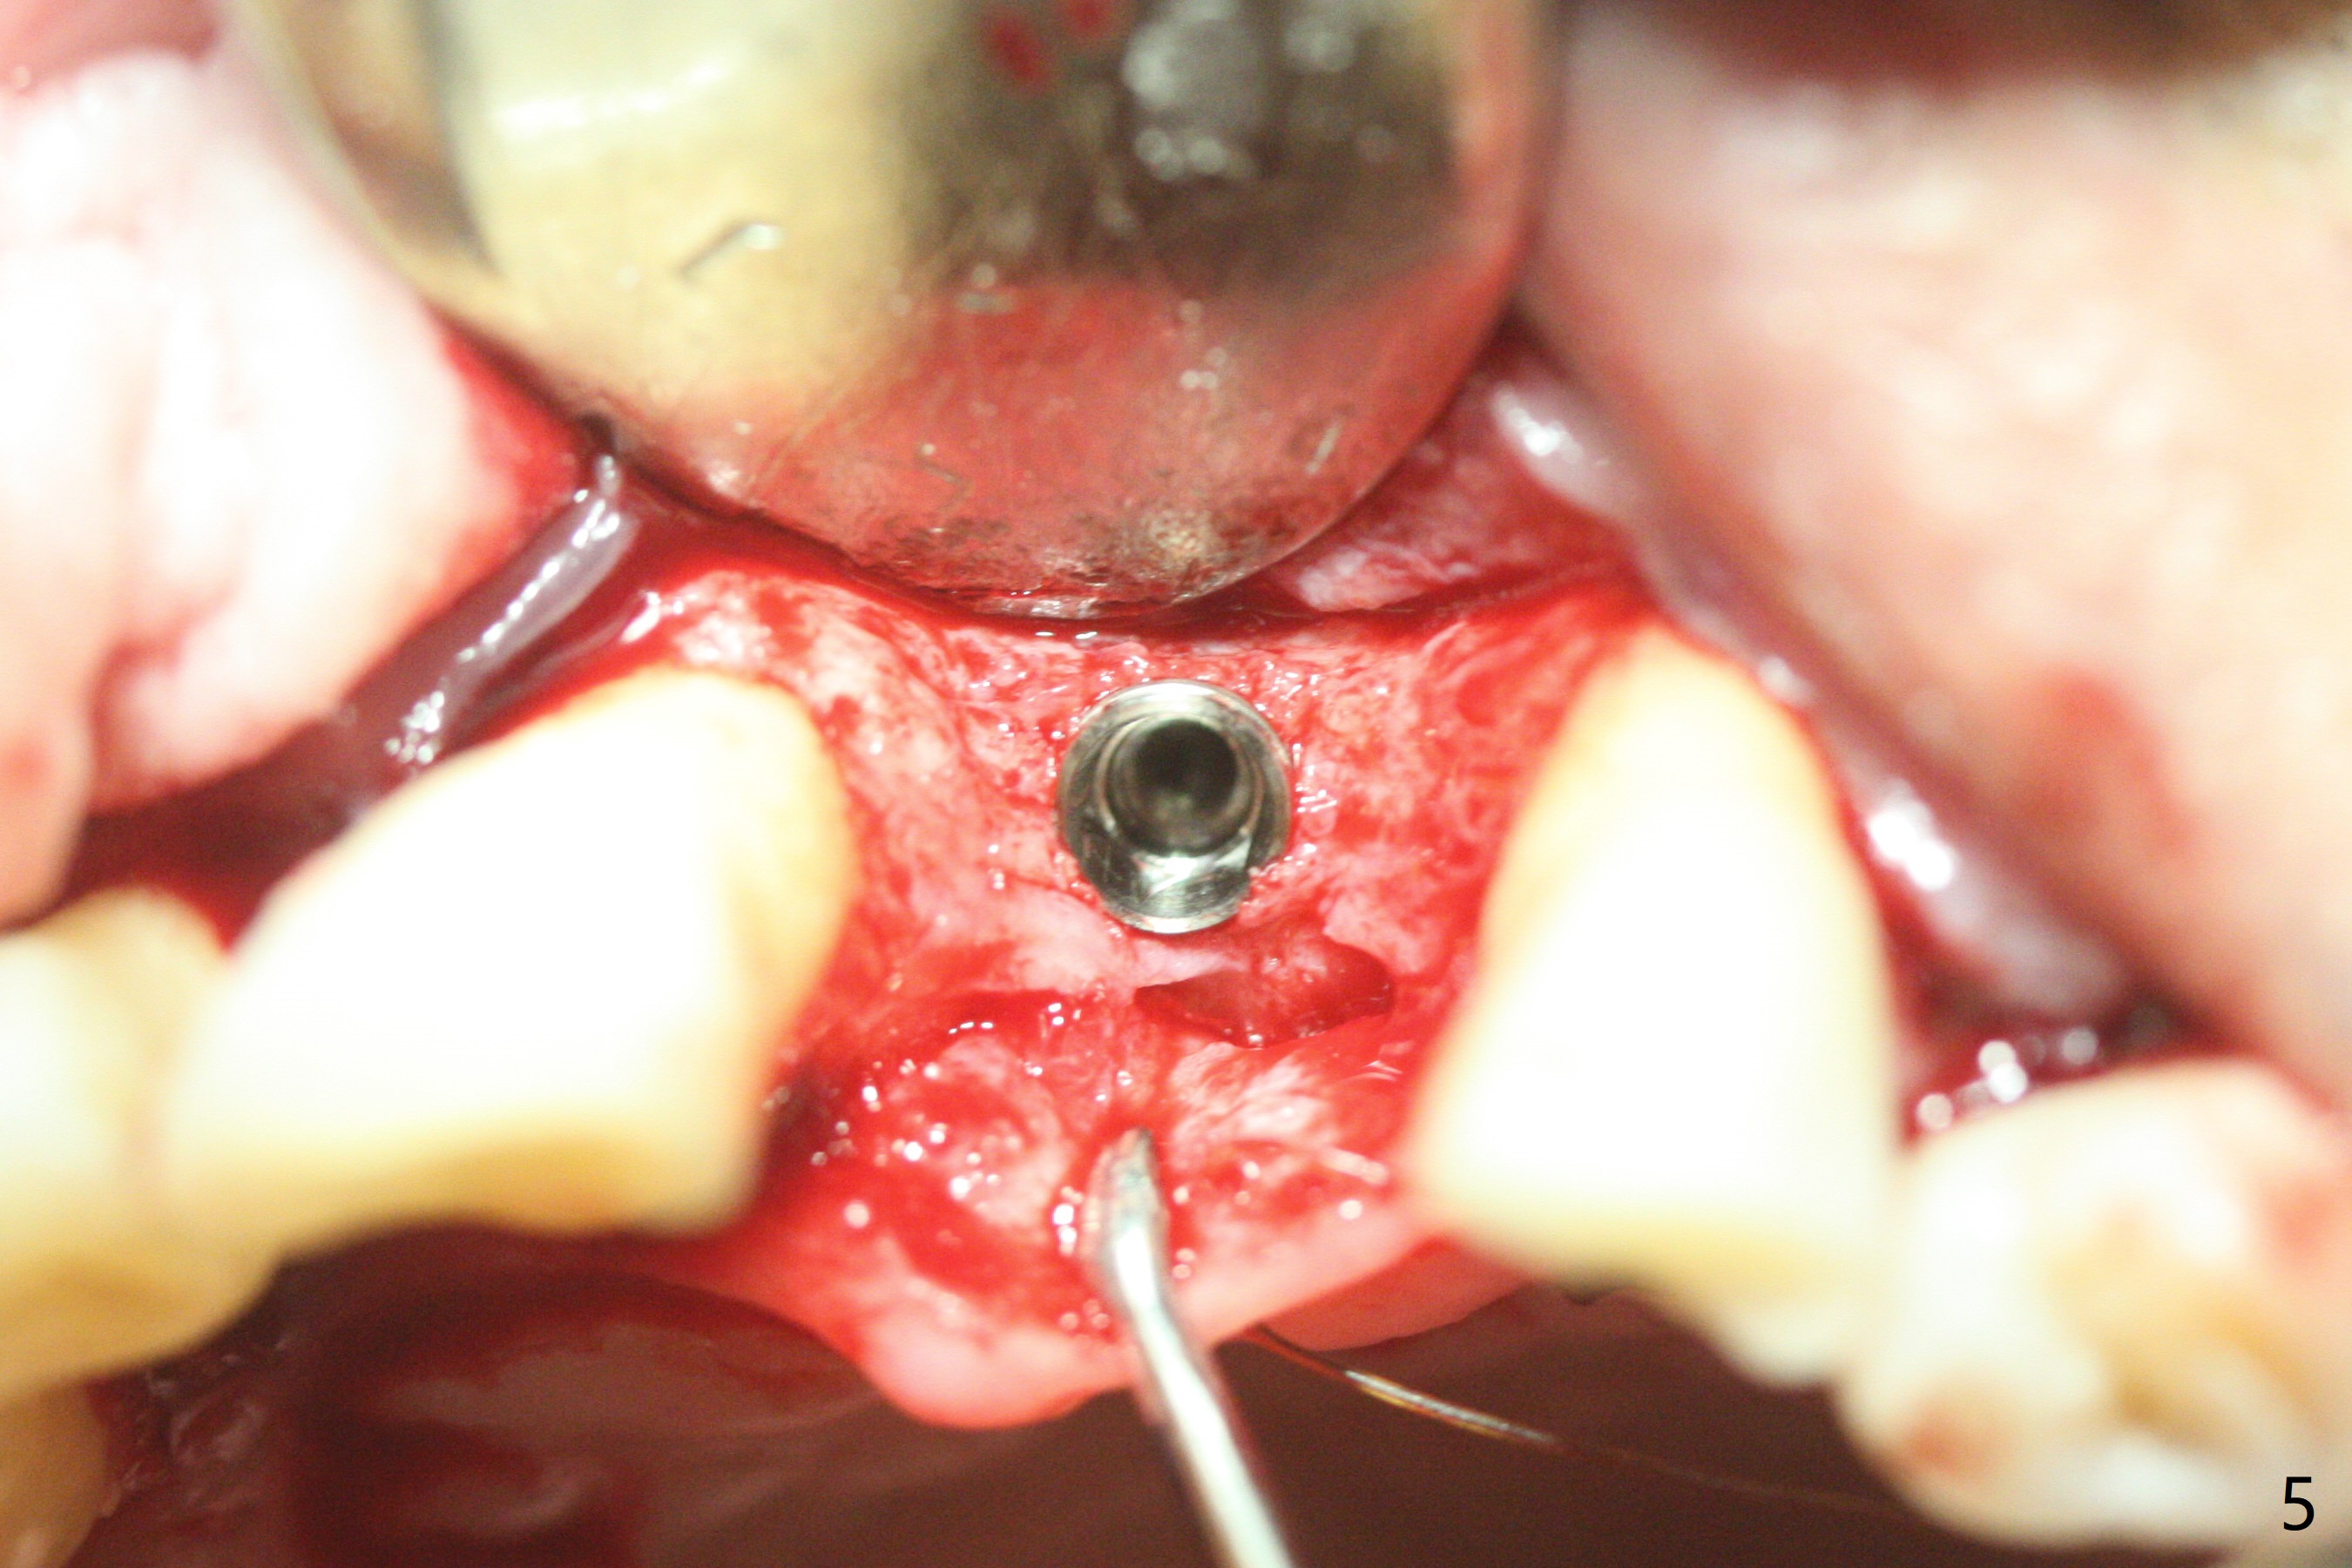

左上1(图一)拔除,植骨,使用带钛架不可吸收膜(图二)后十个月准备植牙(图三),在没有术中根尖片指导下(导板习惯),在牙槽嵴正中开始钻洞,第一个钻头最后一两个毫米觉得有突破感,但是颊侧舌侧没有穿孔,然后植入3.5x11.5毫米植体(图五,扭力>35 Ncm),术后射线表明植体接近切牙管(图四:*)。考虑到病人要离城,颊侧第一螺纹暴露(图六),舌侧骨板薄(图五),植骨,放置愈合基台(图七)。 术后十一天CT显示植体没有侵犯切牙管(图八:I);植体颊侧骨粉(箭头)似乎可以解释颊侧饱满(图九)。第二原因是减张缝合,胶原膜暴露(*),而下面骨粉没有暴露,以后伤口应该是二期愈合。